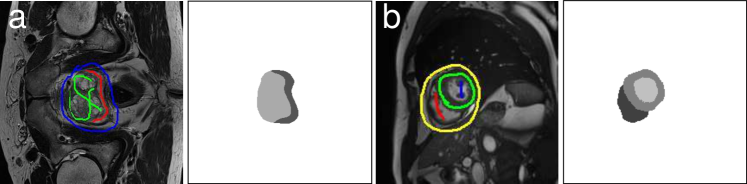

The aim of our proposed method is to learn the parameters θ𝜃\theta of a CNN-based segmentation network 𝐲=f(𝐱;θ)𝐲𝑓𝐱𝜃\mathbf{y}=f(\mathbf{x};\theta) such that it predicts a generally unknown segmentation mask 𝐲{0,,L}N𝐲superscript0𝐿𝑁\mathbf{y}\in\{0,\ldots,L\}^{N} for an input image 𝐱N𝐱superscript𝑁\mathbf{x}\in\mathbb{R}^{N}, where N𝑁N is the number of pixels. During training, rather than full pixel-wise annotations, we are only provided with a ground truth annotation ξ𝜉\mathbf{\xi} for a small number of pixels (i.e. the scribbles). Note that this also includes a background scribble (see examples in Fig. 2). The proposed framework consists of a repeated estimation of the network parameters and subsequent relabeling of the training dataset by combining the network prediction with a CRF. We investigate two different CRF inference strategies: the dense CRF approach proposed in [8], and a recent extension thereof in which the CRF is formulated as a recurrent neural network (RNN) and the CRF parameters can be learned end-to-end [13]. Moreover, we investigate a novel strategy for incorporating prediction uncertainty in the relabeling step based on [7]. For all investigated strategies we perform an initial region growing step described in the following.

Refer to caption

Figure 2: Example images and scribbles on the left and ground truth segmentations on the right for the a) prostate and b) cardiac datasets, respectively.